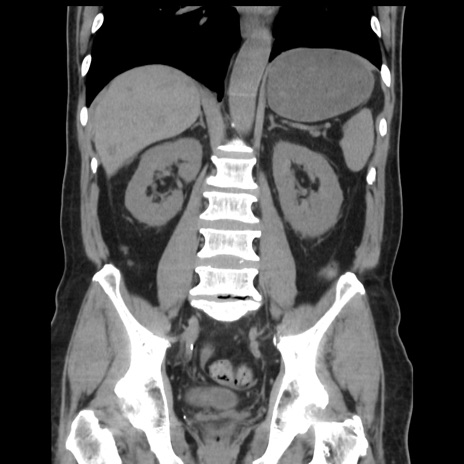

症例16(冠状断像)

【症例】 70歳代男性

【主訴】 腹痛、嘔吐

【現病歴】 約1ヶ月前より間欠的に腹痛と嘔吐あり、当院消化器内科を受診したところCTで多発する肝臓のLDAを指摘され、精査中であった。以降は消化器症状は安定していたが、2日前より嘔気と腹痛があり、同日より排便・排ガスが消失した。改善認めず、 本日、救急外来を受診した。

【既往歴】 大腸ポリープ切除後。

【身体所見】意識清明・会話良好、BT 36.3℃、BP 127/80mmHg、 P 80bpm、腹部:膨満あり、平坦・軟、上腹部正中および下腹部正中に圧痛あり、反跳痛なし、筋性防御なし。

【データ】WBC 7200、CRP 0.77